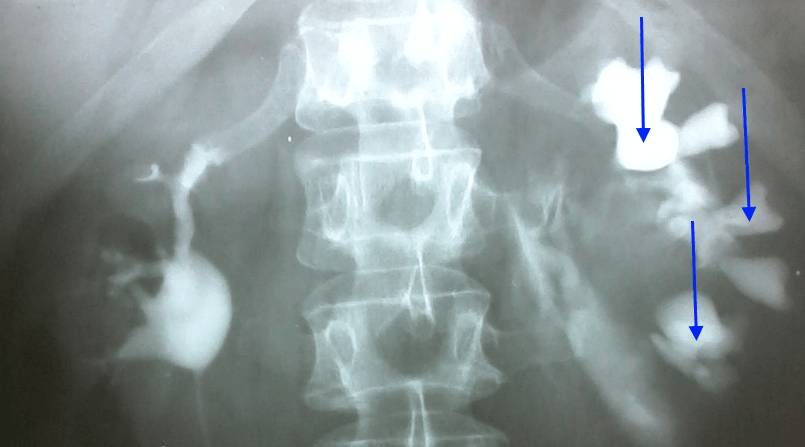

рентгеновский снимок поясничного отдела позвоночника (при остеохондрозе и радикулите имеются характерные изменения позвоночника – остеофиты, межпозвоночные грыжи и др.); общий анализ крови (при заболеваниях позвоночника обычно нет изменений, при болезни почек – лейкоцитоз, анемия, повышение СОЭ); общий анализ мочи (повышенная или сниженная относительная плотность мочи, гематурия, лейкоцитурия, бактериурия, повышенное содержание солей говорят о заболевании почек); УЗИ почек и брюшной полости (увеличение объема почек, наличие в них конкрементов).